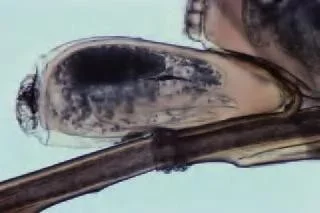

Exam of the Occipital Scalp

Structures on the hair are not freely movable

Exam Findings

Numerous nits (oval egg capsules) firmly fixed to the hair shaft